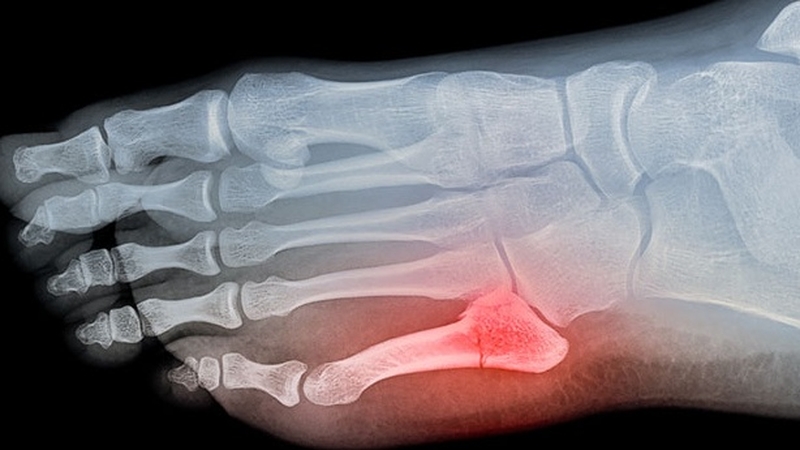

Bong gân ở ngón chân liên quan đến chấn thương dây chằng chứ không phải xương ngón chân của bạn. Dây chằng chính là các sợi mô liên kết gắn các xương với nhau và với các khớp. Bong gân ngón chân út xảy ra khi dây chằng tại đó bị tổn thương, từ đó khiến người bị cảm thấy sưng đau và bầm tím ở ngón chân út. Bong gân có thể xảy ra khi ngón chân va chạm hoặc kéo quá mức đến khi căng ra quá mức trong các chuyển động bình thường hàng ngày.

Bong gân ngón chân út: Biểu hiện, phương pháp điều trị mau khỏi nhất